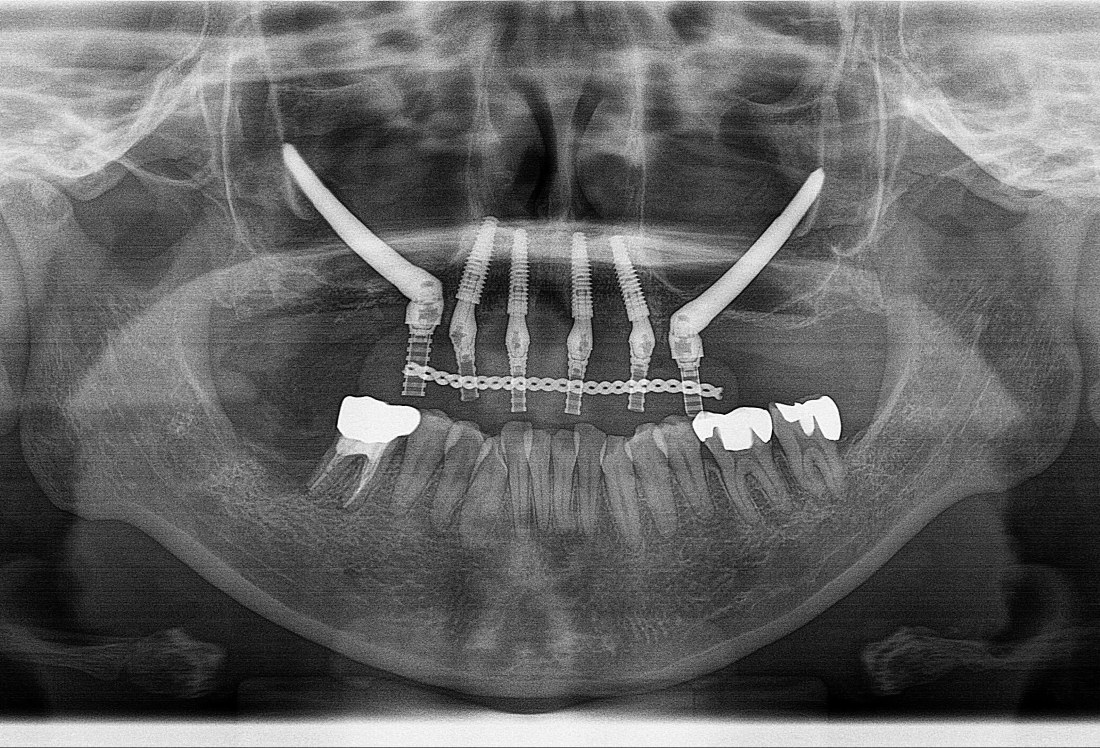

確かに、一般的なインプラント治療と比べると難易度は高い治療です。使用するインプラントの長さも、通常のものが10mm前後であるのに対し、ザイゴマインプラントでは40~50mm程度になります。

また、直接目で確認できない深部を扱うため、解剖学的な理解や術前設計が不十分だとリスクが高まる可能性があります。こうした点から「危険なのではないか」「できる先生が限られる」と言われてきた背景があります。

特に印象的だったのは、進入点・角度・出口を明確に設計する考え方です。「見えないから怖い」のではなく、「見える形にしてから行う」。CTなどの画像診断を用いながら、解剖学的構造を立体的に把握し、無理のないルートを設計するという考え方が徹底されていました。